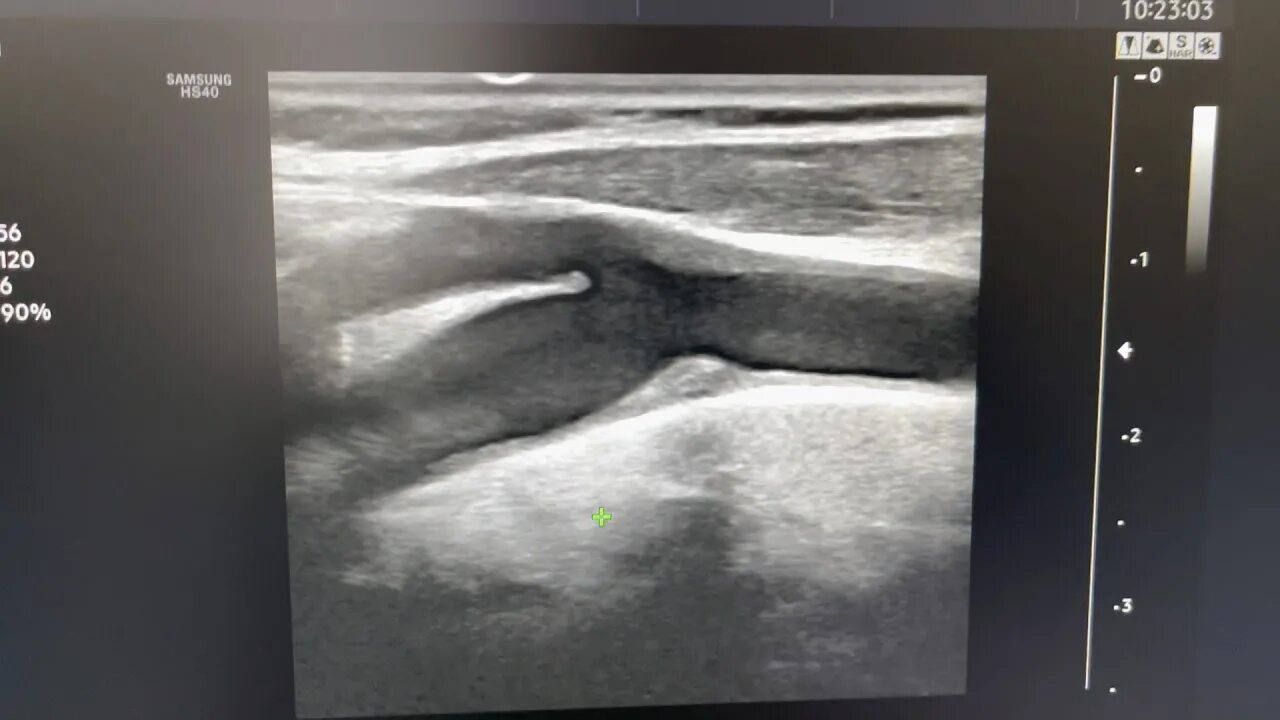

Атеросклеротическая бляшка узи